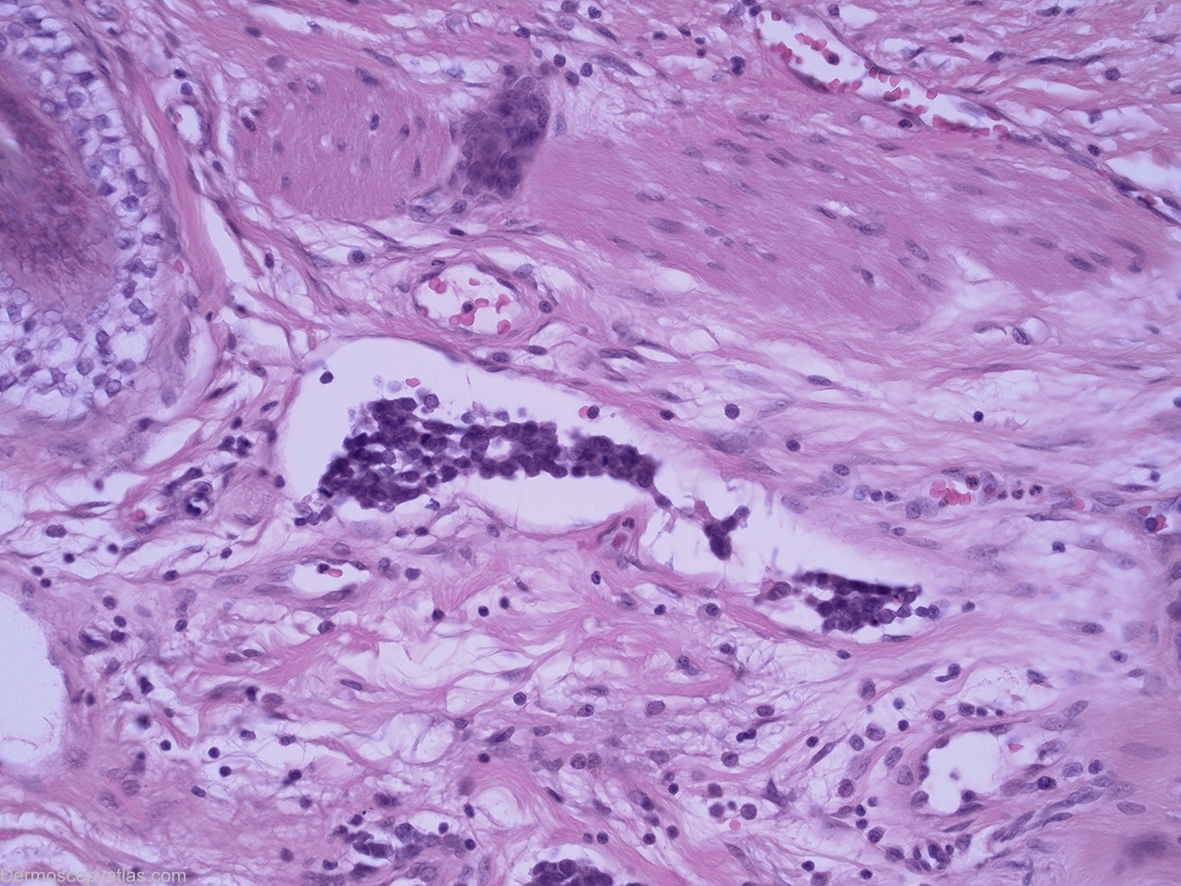

Diagnosis: Merkel cell carcinoma

History: This 83 year old gentleman presented for a routine skin check and this lesion was discovered. Prior to biopsy this lesion was lasered without biopsy by another practitioner but subsequent wide excision of the area discovered a residual dermal based Merkel cell carcinoma at the site where this lesion had been.